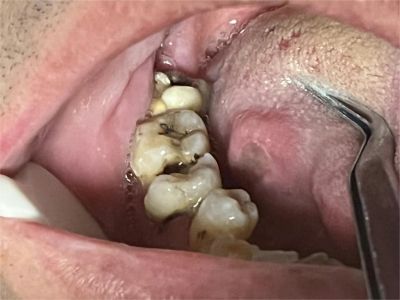

口腔

溃疡

创伤性溃疡口腔溃疡图

创伤性溃疡发生在偏侧颊面的最里侧,有一块肉烂掉,是大牙咀嚼食物时误伤黏膜所致,溃疡面糜烂、发白,有出血,创面面积较大,口腔动作牵扯颊部时疼痛明显。